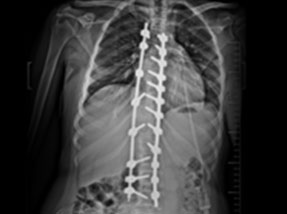

• Post SurgeryAfter

Case 1